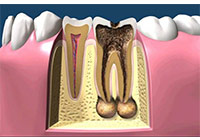

齲齒由口腔中多種因素復合作用所導致的牙齒硬組織進行性病損,表現為無機質脫礦和有機質分解,隨病程發展而從色澤改變到形成實質性病損的演變過程。齲齒是細菌性疾病,因此它可以繼發牙髓炎和根尖周炎,甚至能引起牙槽骨和頜骨炎癥。(圖01~04)

圖3